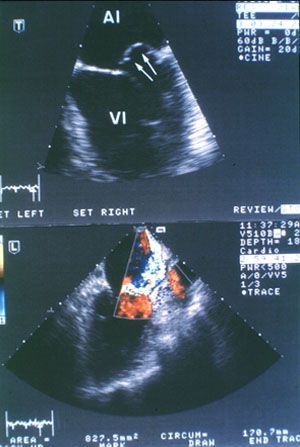

Пролапс митрального клапана (ПМК) - одно из частых заболеваний человека. Он имеется у 3-7% всех людей, причем у женщин встречается в 2-3 раза чаще, чем у мужчин. Суть такой патологии заключается в том, что вследствие разных причин: аномально излишняя величина створок, хорд, папиллярных мышц, митральный клапан провисает в фазу систолы желудочков в сторону предсердия, створки клапана выходят за проекцию клапанного кольца (см. рисунок).

Герметичность клапана при этом чаще сохраняется. Однако у 10% людей, страдающих ПМК, герметичность клапана в той или другой мере нарушена и наблюдается синдром митральной регургитации со всеми гемодинамическими изменениями, свойственными митральной недостаточности (см. резюме случая 1).

Наиболее информативным методом диагностики пролапса митрального клапана является эхокардиография - духмерная и Допплера.

При Допплер-кардиографии возможно не только диагностировать ПМК, но и определить наличие и степень митральной регургитации.

Посмотрите видеоклип Допплер-эхо

Еще один видеоклип Допплер-эхо